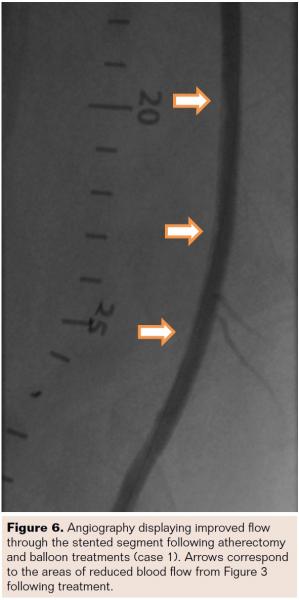

A 78-year-old white female complained of ischemic rest pain in the left leg (Rutherford Class IV; TASC D; ABI 0.40). The patient presented with hypertension, hyperlipidemia, and coronary artery disease. She previously underwent stenting of the mid SFA, distal SFA, and popliteal (P1) arteries 4 months prior. According to core laboratory angiographic analysis, ISR had completely occluded the stented segment with mild calcification present (Figure 7). Lesion length was 350 mm with a vessel with a RVD of 4.21 mm.